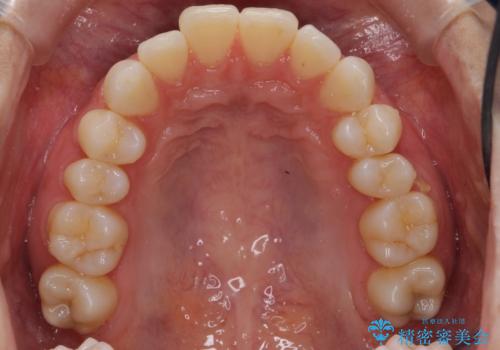

昔ワイヤー矯正をして後戻りした 軽度のがたつき モニター矯正

- 矯正治療後の後戻りを主訴に来院。

マウスピース矯正で再矯正を行いました。